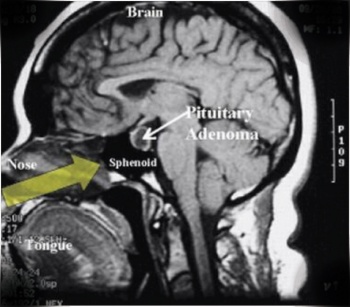

The panhypopituitarism picture prompted MRI pituitary and formal assessment of visual fields by ophthalmology colleagues. The MRI reported a large pituitary mass measuring 24mm by 23mm with significant suprastellar extension, intra-lesional haemorrhage and expansion consistent with pituitary apoplexy. The visual field assessment confirmed the suspicion of bi-temporal haemianopia.

He was urgently transferred to the neurosurgical unit and had trans-sphenoidal hypophysectomy with a good outcome. He is currently on eltroxin and hydrocortisone and is doing well.